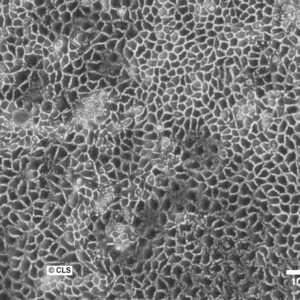

Morphology: Epithelial-like

Growth Properties: Adherent

Description: HuH7 was established in 1982 by Nakabayashi et al. from a 57-year-old Japanese male with well differentiated hepatocellular carcinoma.